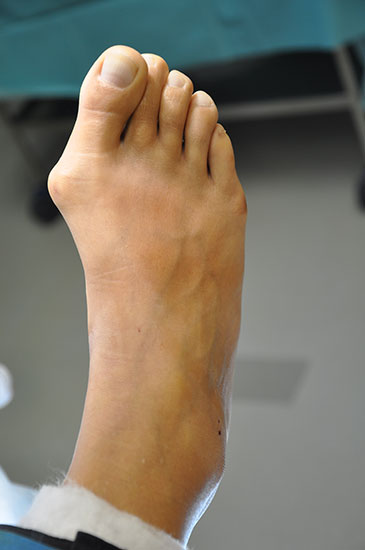

Der Hautschnitt über den Metatarsaleköpfchen verläuft quer oder längs - bei kontrakten Weichteilverhältnissen empfiehlt sich ein z-förmiger Hautschnitt. Die Gelenkkapsel wird längs gespalten unter Schonung der Strecksehnen. Bei der anschliessenden Mobilisation der Gelenkkapsel und der periartikulären Weichteile sollten die Kollateralbänder geschont werden. Die Osteotomie (siehe Video) sollte parallel zur Fußsohle verlaufen und eine maximale Verkürzung von 3 mm vorgenommen werden (Rotationsachse!). Nach Osteosynthese der Osteotomie mit regelrechter Einstellung der Gelenklinie des Mittelfußköpfchens wird der knöcherne Überstand abgetragen, die Gelenkkapsel wiederverschlossen und die Strecksehnen rezentriert (Myerson, 2005).